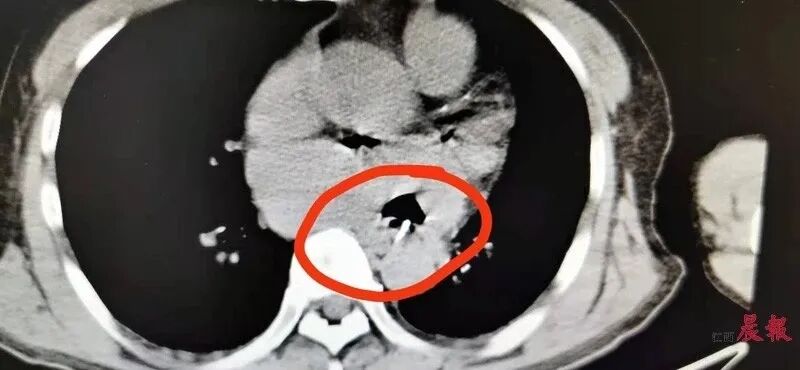

就在前几天,抚州的胡先生真正体会到了什么叫做“祸从口入”:胡先生吃鱼时被鱼刺卡住了喉咙,用尽喝醋、咽饭团等各种“土办法”化解,结果咽下去的鱼刺一路刺破食道并刺入心脏,险些危及性命。

影像学检查报告显示,一块2厘米长的异物牢牢刺入食道中,甚至还刺入了患者的心脏。图片来源九派新闻我们习惯了源源不断地吞下食物,因此很少人能意识到,食物的摄入到排泄其实是一场漫长而艰巨的旅程。加上人类什么都敢往嘴里塞的坏习惯,稍有不慎,就会带来一场飞来横祸:食物或异物,滞留在肚子里的各种弯道窄巷里了。这种疾病学术名叫“消化道嵌顿”,只要人类还在吃东西,就有患病的风险。医学发展到今天,前人用血泪为我们总结出了以下几个凶险的难关……